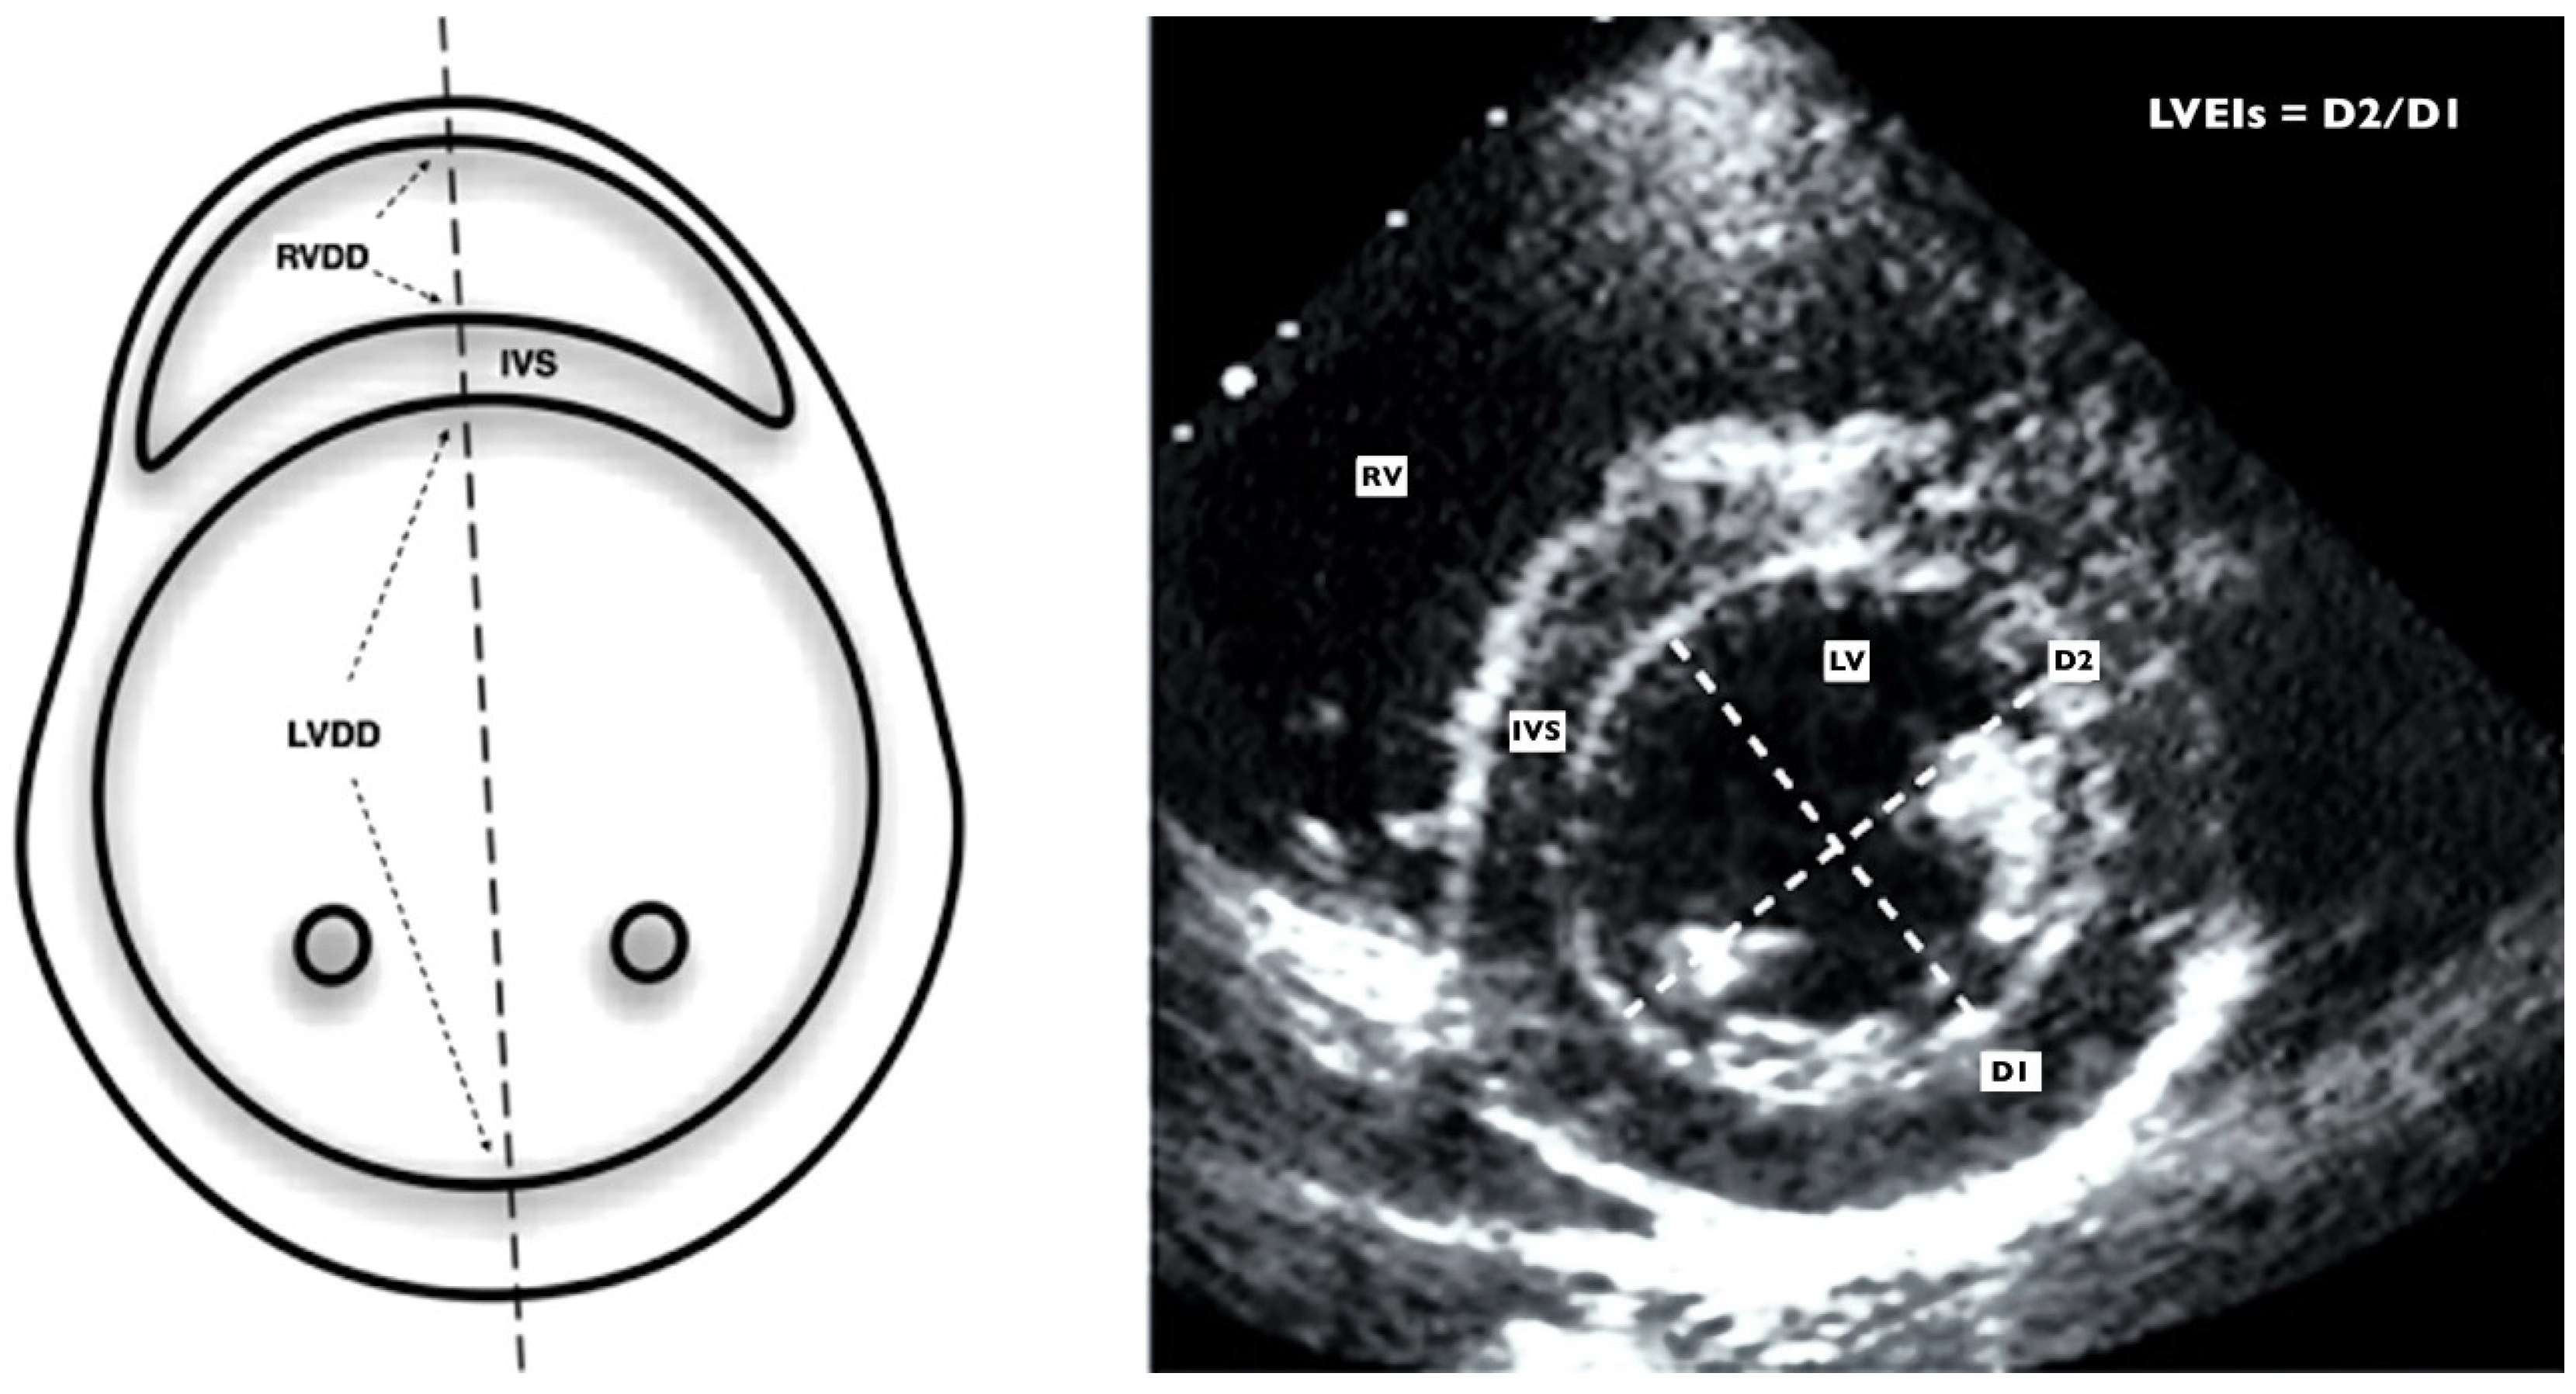

- Abraham, S.; Weismann, C.G. Left Ventricular End-Systolic Eccentricity Index for Assessment of Pulmonary Hypertension in Infants. Echocardiography 2016, 16, 910–915. [Google Scholar] [CrossRef] [PubMed]

| LVEI | 1.08 (0.98–1.45) | 1 (0.95–1.12) | <0.001 |